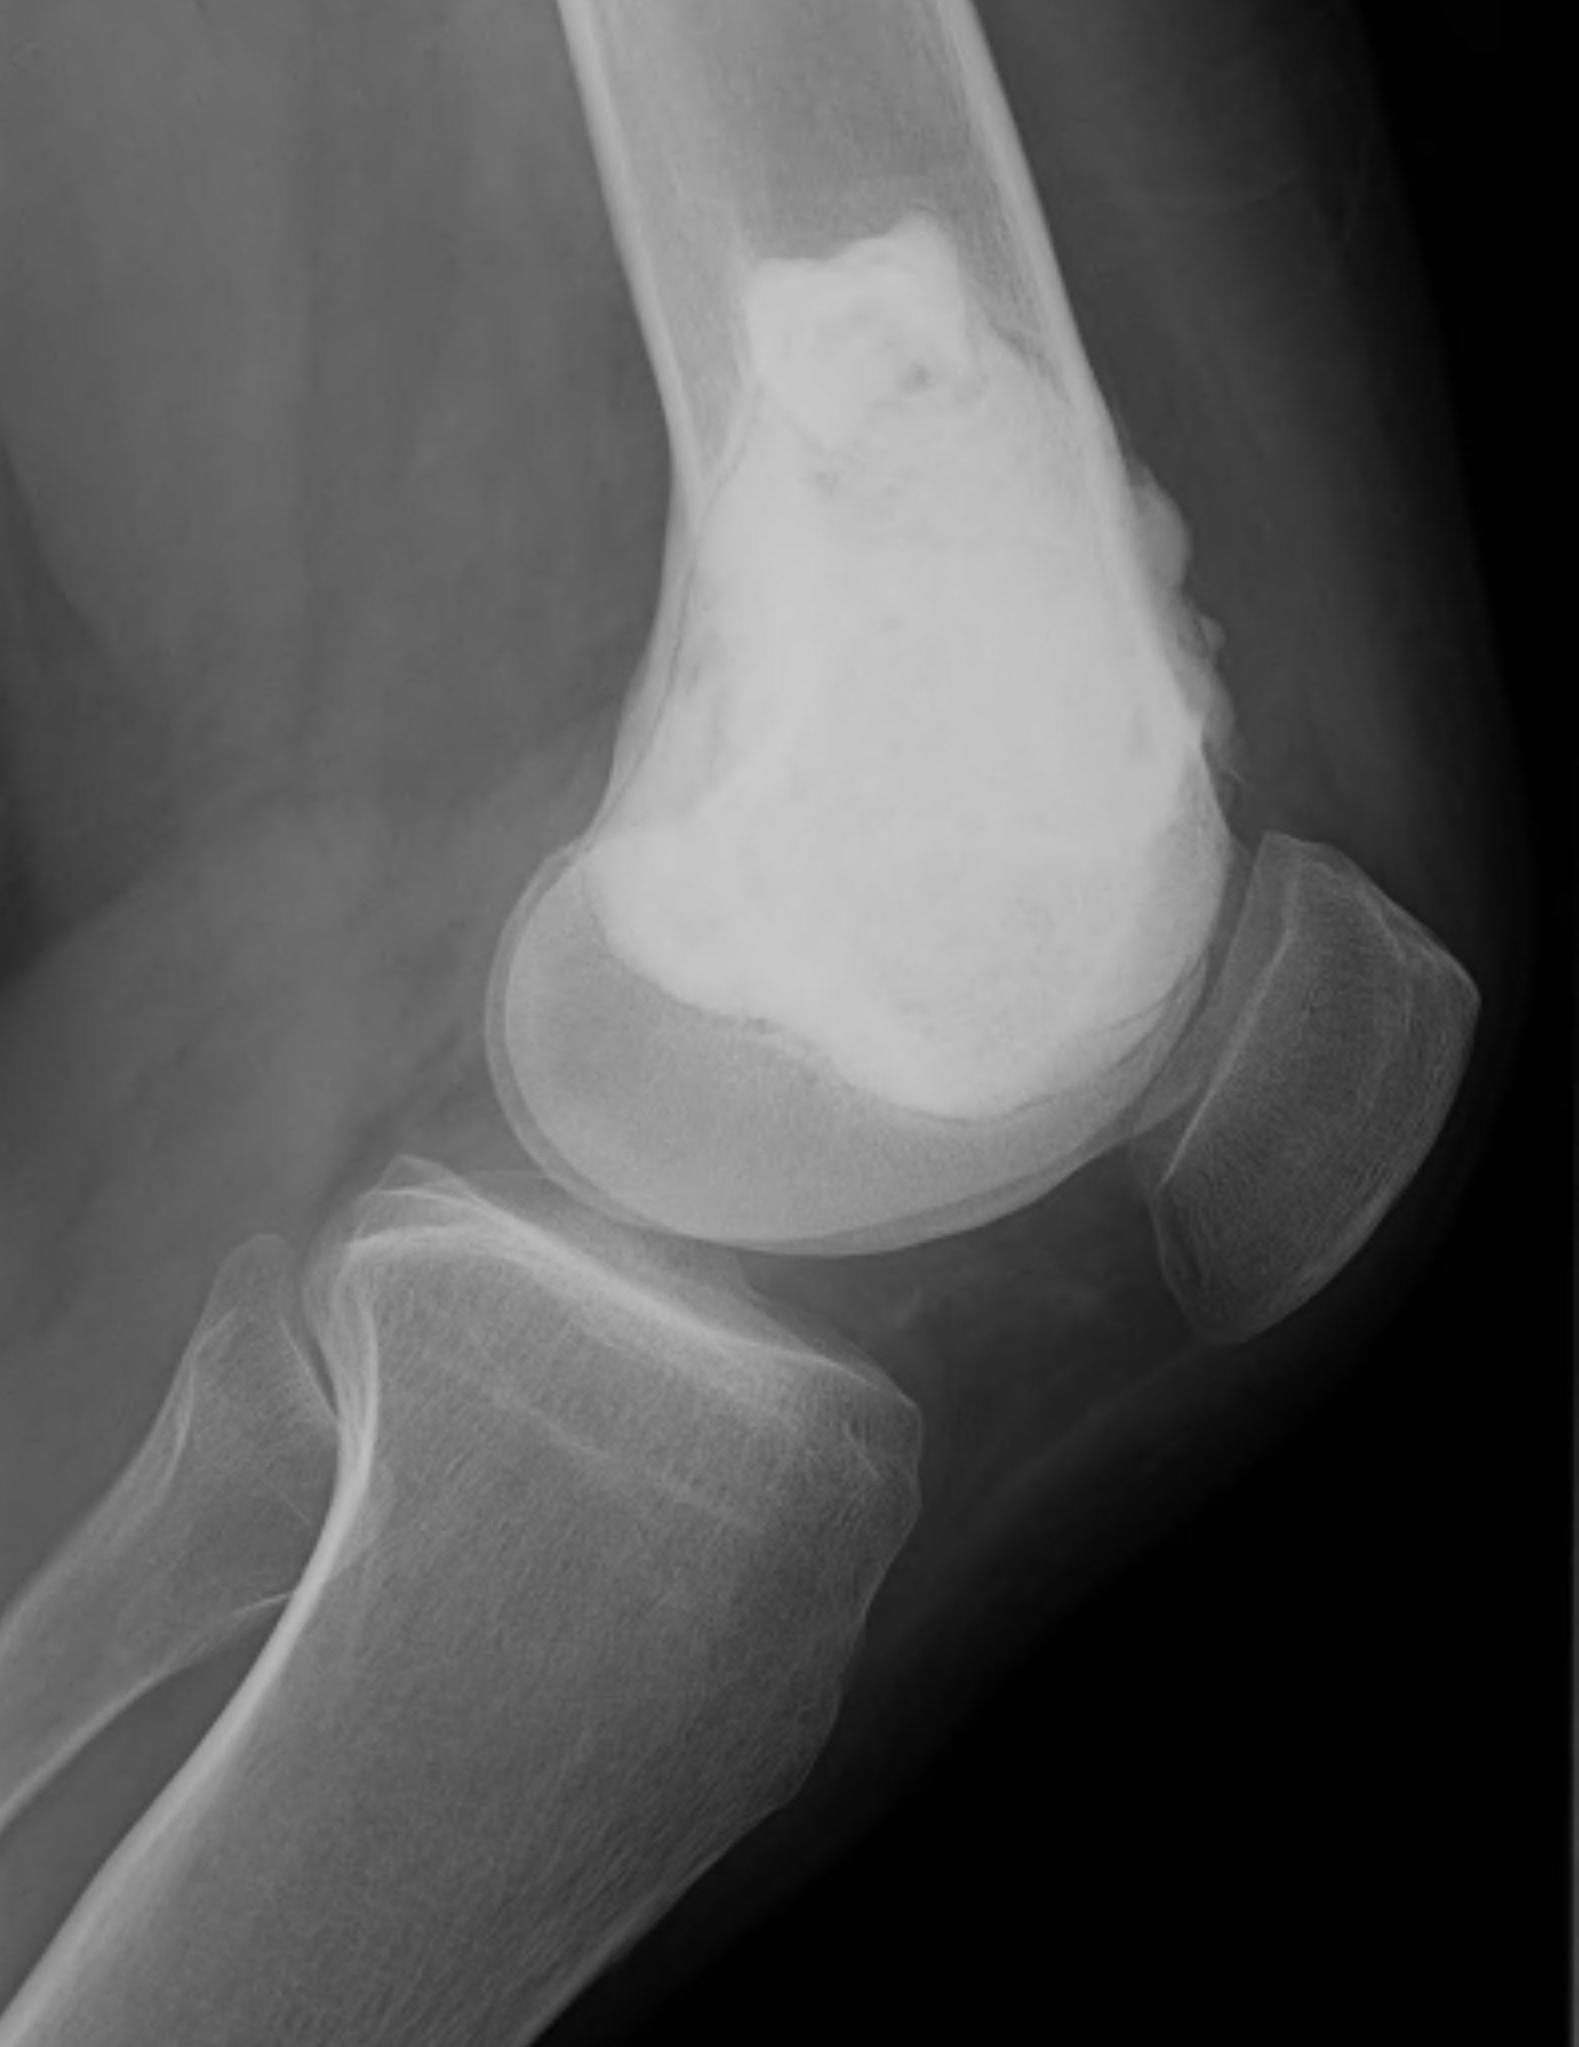

X-ray

Eccentric, sharply demarcated lytic lesion

- no sclerosis around lesion

- narrow zone of transition

- metaphysis, extending into epiphysis

- no mineralization